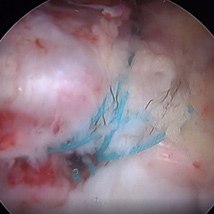

Minimally invasive surgery can be performed either through one small incision in the lateral hip or through 3-4 poke-hole incisions with the use of a camera and special instruments. The damaged trochanteric bursa is removed. The tendons are reattached to the lateral hip (greater trochanter) with suture anchors.